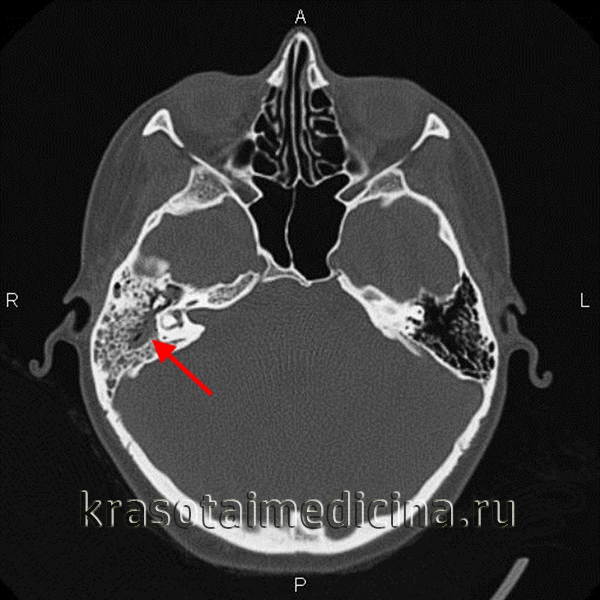

Компьютерная томография височных костей, на которой определяется

распространенное образование верхушки правой пирамиды с тонкими костными стенками.